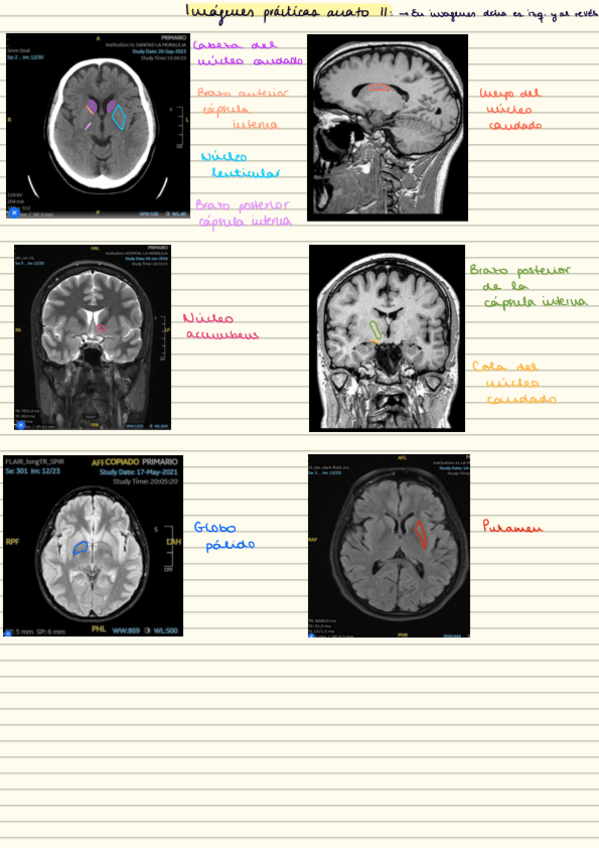

practicas-imagenes-resonancias.pdf